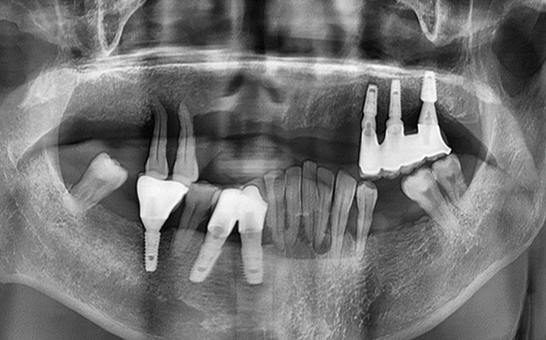

CASE 01 김** / 60대

전악임플란트

치료 시작 전 촬영 2024.01.24 | 치료 완료 후 촬영 2024.12.26

1 예후불량 치아 발치

2 발치 후 즉시 임플란트 식립 및 뼈이식

3 고정성 보철물로 수복 후 일상 회복